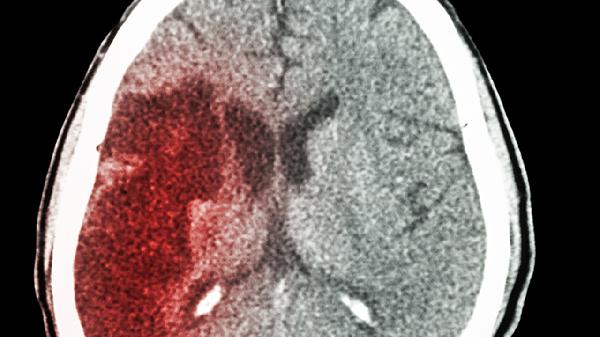

每多吃一次,脑梗就近一步?医生提醒:这4物是脑血管的 “杀手”

脑梗这个"隐形杀手"悄悄盯上了越来越多年轻人!最近门诊遇到个32岁的程序员,熬夜加班时突然半边身子不能动,送到医院确诊脑梗。翻看他手机里的外卖记录,清一色都是高油高盐的"催命套餐"。其实日常饮食中藏着不少脑血管"刺客",有些甚至伪装成健康食品。